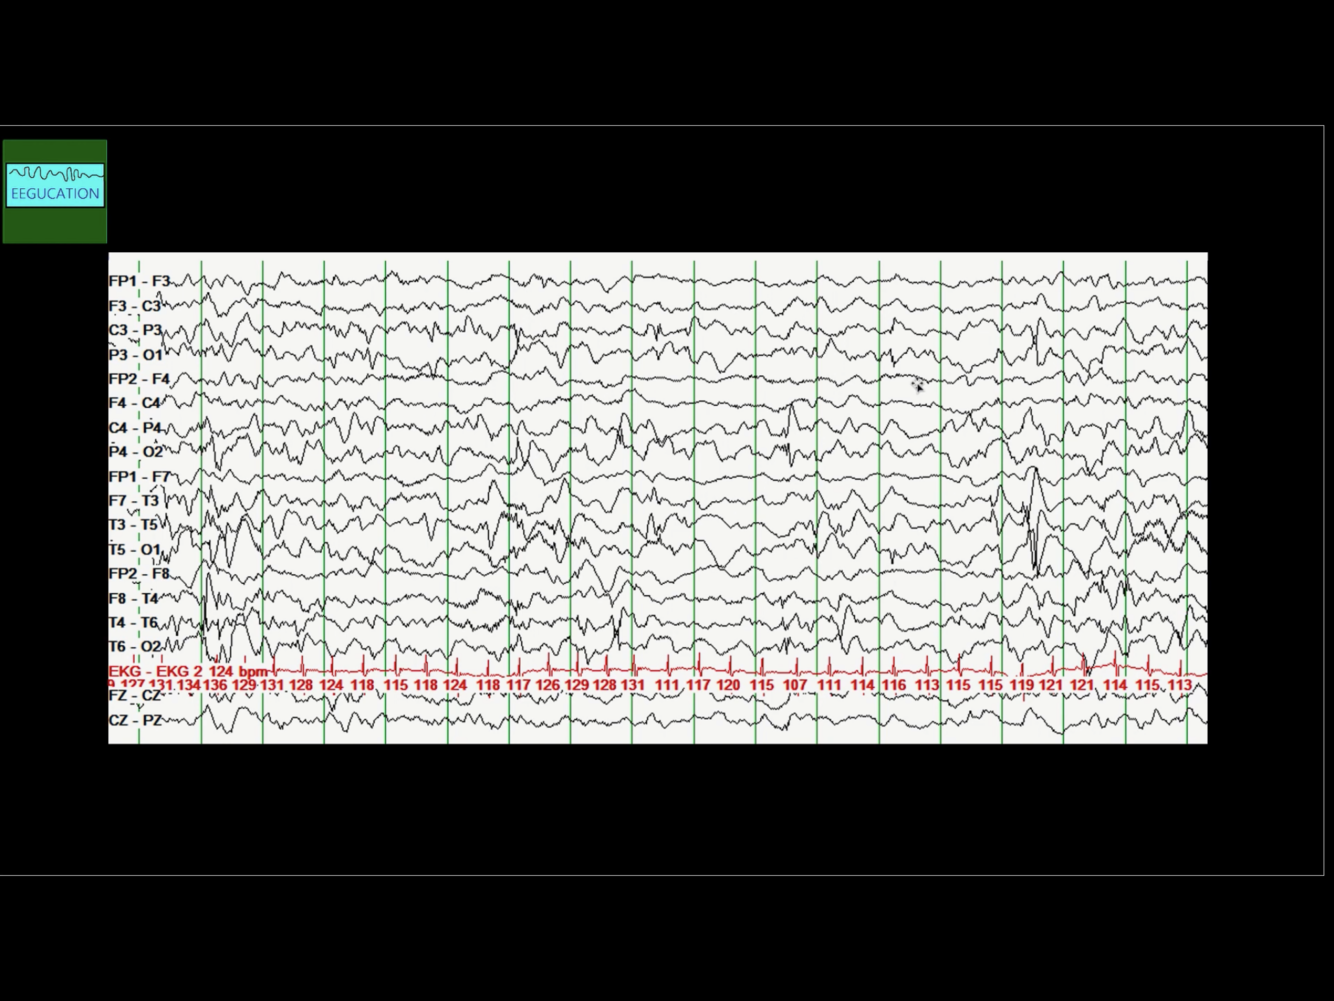

Diagnosis?

Photoparoxysmal response

What is the general interpretation of photoparoxysmal response?